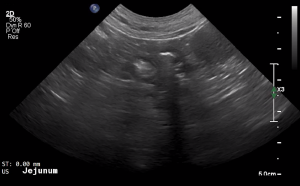

SIMON Ultrasound Database

This ultrasound database is a free resource for students and doctors!

Our collection includes videos of dogs, cats, horses, cows, humans, and many other species!

–Canine and Feline abdominal ultrasound videos were generously provided by the Cummings School of Veterinary Medicine at Tufts University.